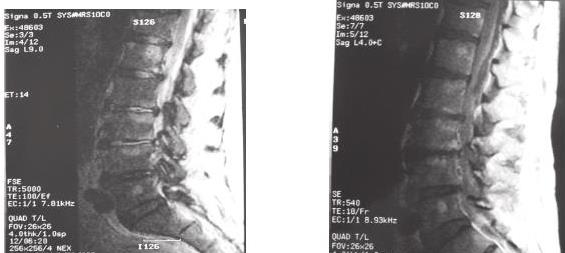

El dolor lumbar es una afección muy frecuente en la población. El absceso espinal epidural no tuberculoso (AEE) como etiología de la lumbalgia es excepcional; su importancia radica en las dificultades diagnósticas existentes y en su elevada morbimortalidad en caso de no ser tratado precozmente.

Se analiza la historia clínica de un hombre de 63 años, con antecedentes de diabetes y lumbalgia mecánica, que tras concurrir en reiteradas oportunidades al servicio de emergencia por exacerbación de su dolor habitual se le diagnóstico un AEE a estafilococo aureus meticilino sensible. Fue dado de alta al domicilio a los 25 días del ingreso con recuperación ad integrum.